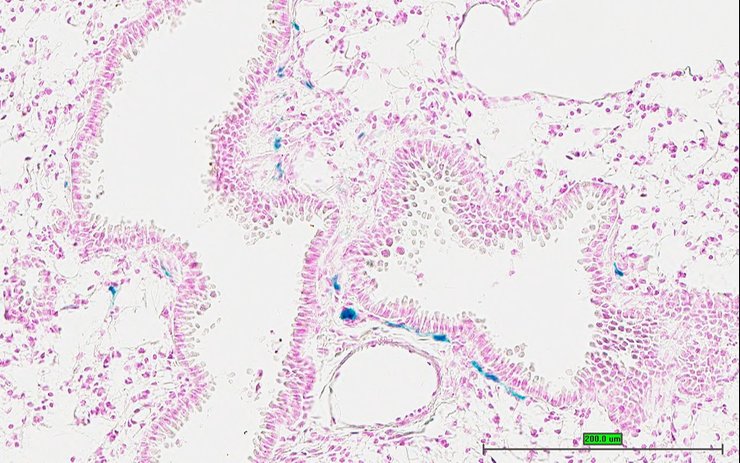

TS28: lung Present UC Davis_1876087

Specimen UC Davis_1876088: postnatal adult; Kcna1tm1.1(KOMP)Vlcg/Kcna1+ (more )

TS28: lung Present UC Davis_1876088

TS28: lung Present UC Davis_1876021

Specimen UC Davis_1876022: postnatal adult; Kcna1tm1.1(KOMP)Vlcg/Kcna1+ (more )

Structure Level Pattern Image Note

TS28: lung Present UC Davis_1876022

Specimen UC Davis_1876023: postnatal adult; Kcna1tm1.1(KOMP)Vlcg/Kcna1+ (more )

TS28: lung Present UC Davis_1876023